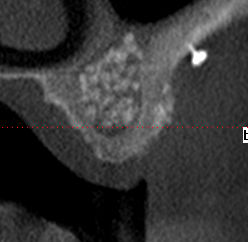

26/04/2010 à 14h00

la suite radiologique du cas, implantation prévu le 6 mai

Biobank   6 mois dbkbbo - Eugenol

Biobank 6 mois  2 cj54ky - Eugenol

Biobank 6mois 3 ck56hx - Eugenol

Biobank 6 mois 4 giwlus - Eugenol

Post1 y45ukn - Eugenol

Post2 caxl5b - Eugenol

Post3 ovhzhy - Eugenol